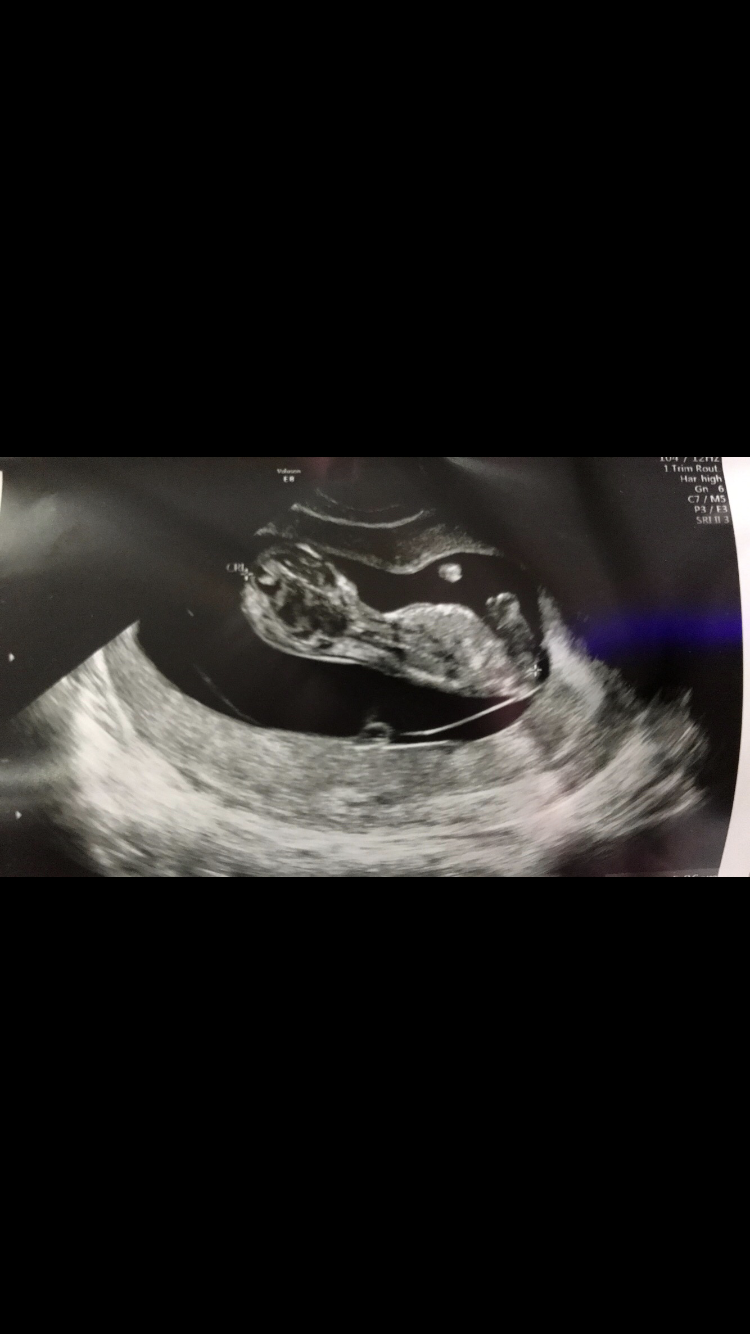

هذه صورة سوناري في الأسبوع ١٢

بان معك الجنس 😻😅 ؟!